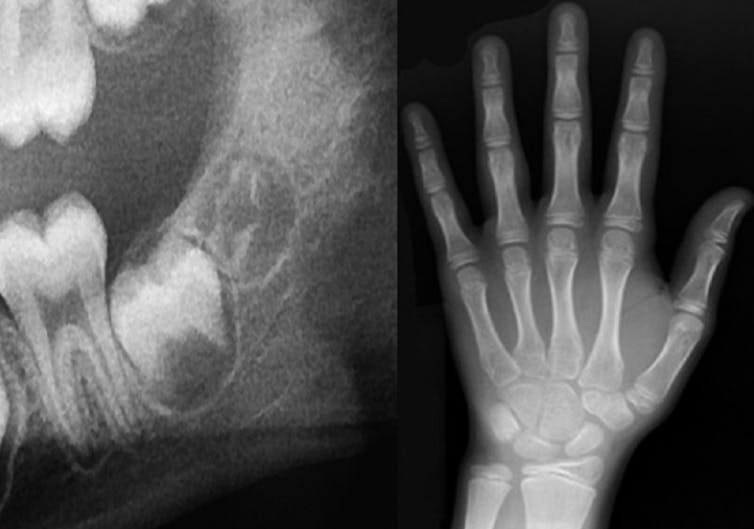

For children and teenagers, such an analysis can be carried out by examining X-rays. Growth and development are predictable processes, and milestones occur in a particular order. This is the reason that a tooth such as the first adult molar is also known as the “six-year molar,” because it generally erupts in everyone around age 6, give or take.

The analysis proceeds the same way whether we’re examining the X-rays of a living or deceased person. Essentially, we compare the stage of growth shown in the X-ray to existing growth charts from children and teenagers of known ages.

The crucial point is that it’s not possible to make a definitive, single age determination from X-rays or examination of bones or teeth. A variety of factors affect how well chronological age corresponds with biological age; that is, the amount of time since birth doesn’t necessarily correlate to the exact same stage of growth in every child or teenager.

Therefore, forensic anthropologists report age estimations as a range. For example, rather than saying someone is 17 years and 8 months old, our estimation may be that she is between 17 and 20 years old.

Sometimes, the estimated age range might include ages below and above 18. Take the development of the wisdom tooth, something we often look at when estimating age of older teenagers and young adults. But the development of this tooth is extremely variable, ranging from never developing at all to erupting anywhere from the mid-teens to early 20s. In such cases, how would a final decision of adult or minor status be made?